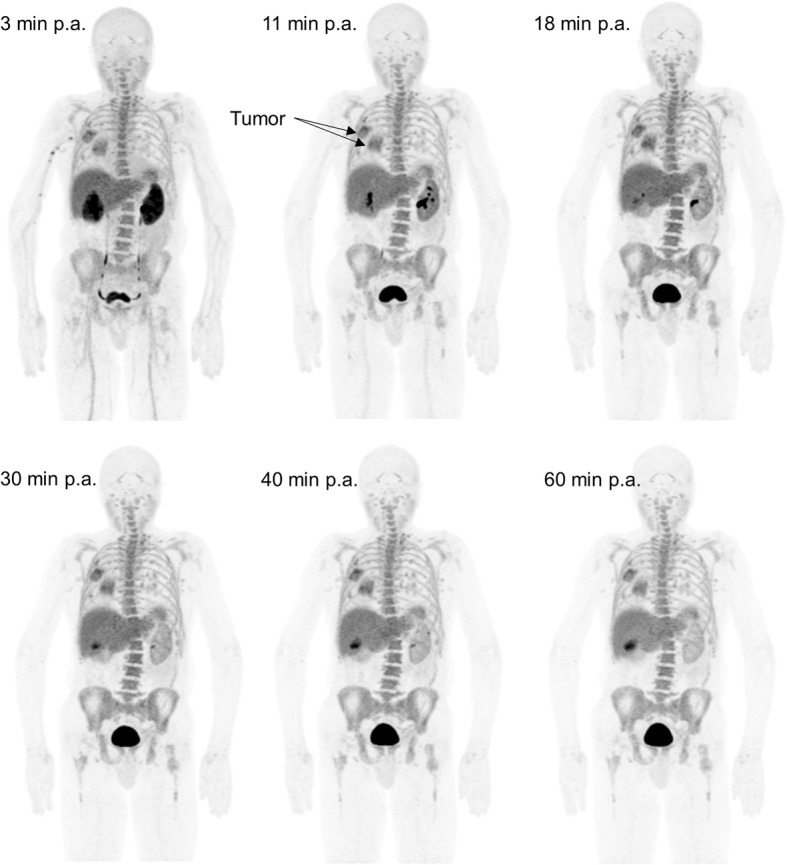

Fig. 1.

Example of maximum intensity projections 3, 11, 18, 30, 40, and 60 min post-tracer administration (p.a) showing in-patient 18F-Azafol activity distribution

A typical biodistribution of 18F-AzaFol is shown in Fig. 1 (MIP images at 60 min for the six patents are shown in Figure S4 of Supplemental Data 4). The main way of biological excretion of the radiopharmaceutical from the body was through the urine. Prominent kidney uptake was visible in the early phase followed by rapid renal wash-out. Significant urinary bladder activity accumulation was seen as early as 10 min after injection. A significant uptake was observed in the choroid plexuses from the early time point images (Fig. 2).